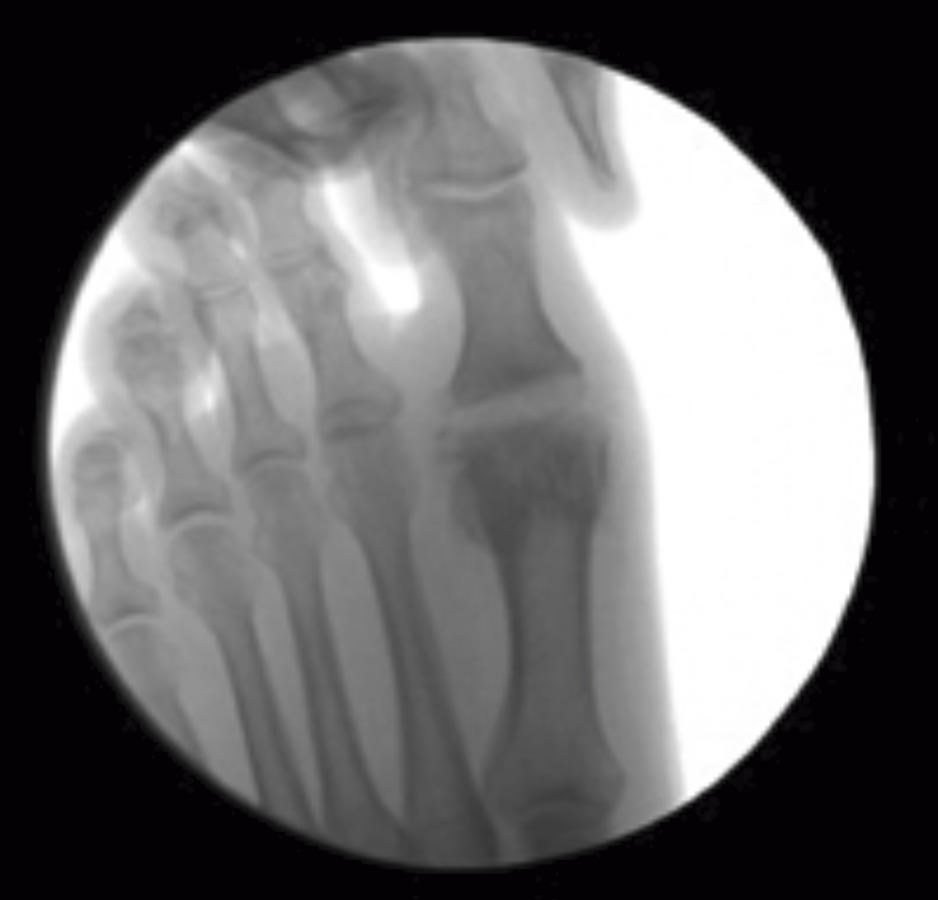

Se debe acceder a la articulación mediante 1 o 2 portales articulares situados a ambos extremos de la articulación a nivel dorsal (Figura 1). Deben ser unos portales un poco más grandes de lo normal, de 2 a 3 mm, que nos permitan un buen acceso a la articulación y poder extraer los fragmentos de cartílago que no podamos triturar. La fresa a utilizar es la Shannon® larga o Shannon® 44, que permite acceder a toda la articulación (Figura 2). En ocasiones, podemos utilizar la fresa de tipo pino (llamada así por su forma).

Figura 2. Cruentación de las superficies articulares con la fresa Shannon® bajo control radiológico.

Se debe ser muy ordenado y cruentar bien la superficie articular de la cabeza del metatarsiano y, después, de la falange. Al utilizar una fresa y no una sierra, es posible realizar mínimas resecciones óseas. Esto es especialmente útil cuando la falange es muy pequeña, por ejemplo, en secuelas de intervención de tipo Brandes-Keller.

Podemos hacer distracción del dedo para ir resecando fragmentos de cartílago, los cuales se extraen por el portal. Una vez resecado el cartílago, se cruentan las superficies articulares (Figura 3). La papilla ósea, al ser muy osteogénica, se deja en la articulación.

Figura 3. Distracción de la articulación. Superficies articulares preparadas para la artrodesis.